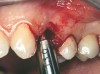

A 53-year-old female was referred for evaluation of a fracture of tooth No. 24. The tooth had been treated endodontically 5 years prior. The radiograph revealed a complete fracture of the tooth involving the crown (Figure 12). Tooth extraction and immediate placement of a an implant that was 10 mm in length and 3.75 in diameter was planned.

At the time of surgery, the tooth was extracted without harvesting any mucosal flap because the implant site was prepared by means of a pilot drill bur (Figure 13) and alternating osteotomes (Figure 14A and Figure 14B). The implant was positioned and showed primary stability. The implant was loaded 2 days after surgery. Then, splinted PFM crowns supported by custom gold abutments were delivered. At 6 months posttreatment, the radiograph revealed no bone resorption and the clinical result was optimal (Figure 15A and Figure 15B).

Figure 13  The drill bur was used to start the implant site preparation.

Figure 13